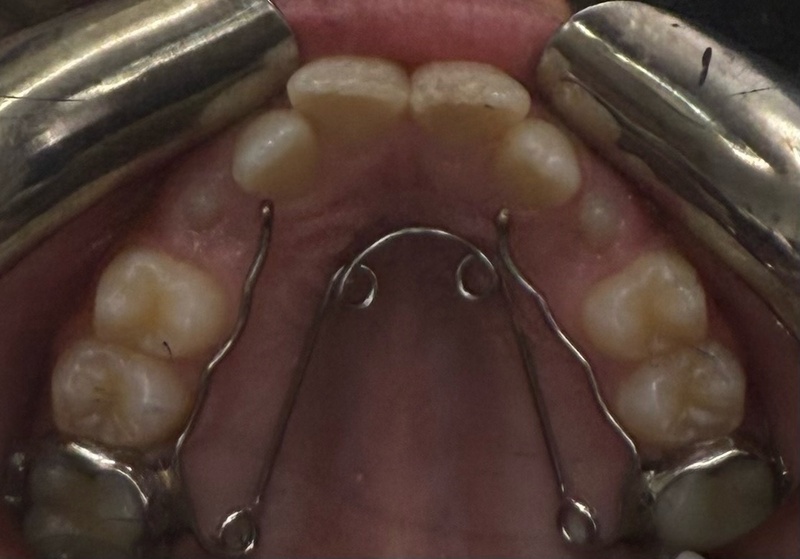

Elle peut s’accompagner d’une prise en charge orthopédique pour améliorer le développement des mâchoires par le biais d’appareils amovibles ou fixes